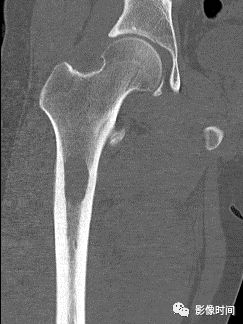

九、瘤周水肿

肿瘤周边的骨髓水肿表现为 T1WT 低信号和 T2WI、STIR 高信号边界模糊的片状影,软组织肿块邻近的正常软组织成分,尤其是肌肉内亦可出现水肿,表现为肿块周围沿肌束方向分布的边界模糊的片状或羽毛状影,有时可连成片。瘤周水肿常见于恶性肿瘤(图 58),但也可见于某些良性肿瘤如软骨母细胞瘤(图 59)、骨样骨瘤和骨嗜酸性肉芽肿(图 60)等。

图 60  瘤周水肿:骨嗜酸性肉芽肿